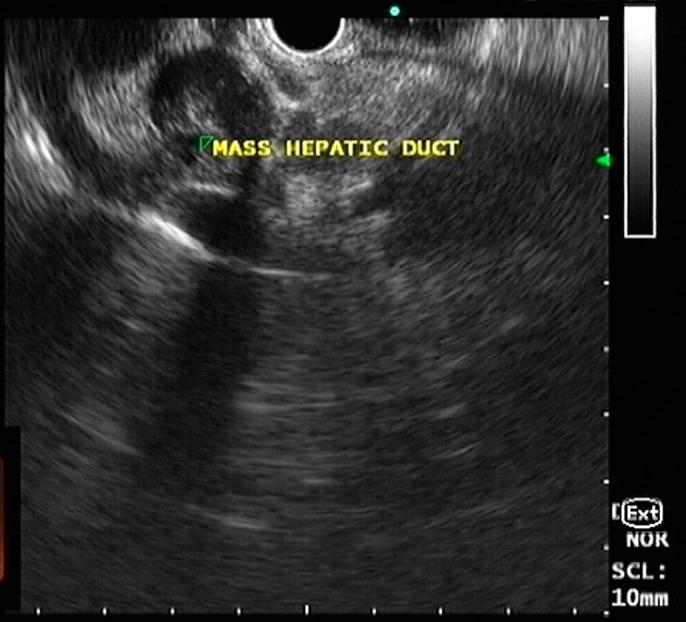

Jack in the Duct: A Case of Common Biliary Duct Schwannoma.

https://cdn.ncbi.nlm.nih.gov/pmc/blobs/2446/6855524/2a50c1420358/ac9-6-e00223-g001.jpg